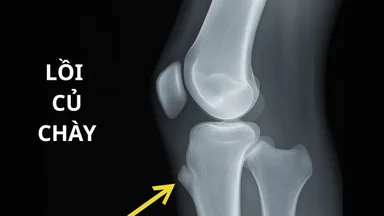

Hội chứng Tennis elbow hay còn gọi là viêm lồi cầu ngoài xương cánh tay là chấn thương thường gặp ở người hay chơi thể thao. Đây là tình trạng viêm hoặc rách của khối gân cơ duỗi tại vị trí bám của gân cơ vào mỏm lồi cầu ngoài xương cánh tay.